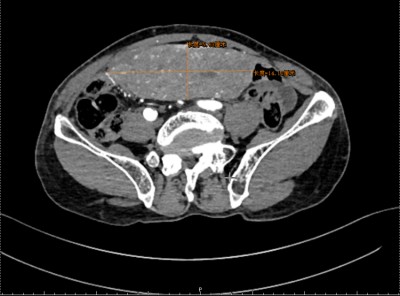

魏嵩为其完善检查进一步明确诊断,腹部增强CT结果证实:阑尾未见明确异常,但于腹盆腔内见一直径约15厘米的巨大占位性病变。

该病灶内部伴出血,并与肠系膜血管、膀胱、右半结肠及部分小肠广泛粘连、分界不清,已对周围脏器及血管形成显著压迫。整个影像学表现提示其侵袭性强,手术难度及风险极高!